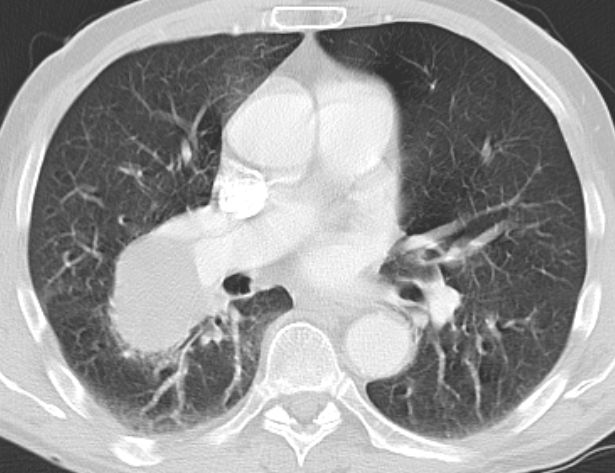

64-jähriger Mann mit plötzlich aufgetretener Luftnot. Inzwischen Sauerstoff - abhängig.![]() |

![]() | |||

![]() |

![]() | ||||